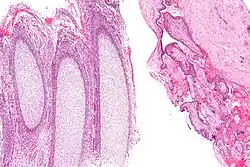

Micrograph of products of conception. Chorionic villi (right of image) and cartilage, i.e. fetal parts (left of image). H&E stain.

On gross pathology, the presence of chorionic villi (left) is diagnostic of products of conception, whereas decidua (right) is not.